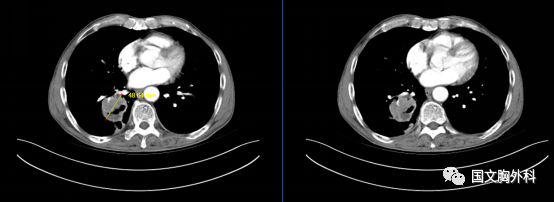

入院時胸部CT,提示:胸部CT平掃+增強:右肺下葉占位,符合肺癌表現(xiàn),伴周圍阻塞性肺炎??v隔、右肺門稍大淋巴結(jié),轉(zhuǎn)移不除外。

治療前 ↓